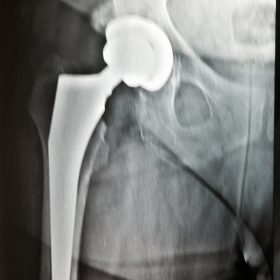

Παραδοσιακά οι αρθροπλαστικές ισχίου αποτελούνται από μια μεταλλική μπάλα – σφαίρα τοποθετημένη σε μια πλαστική κοιλότητα (κοτυλιαία πρόθεση).

Η πλαστική επιφάνεια στήριξης φθείρεται με την πάροδο του χρόνο, με ρυθμό μάλλον σχετιζόμενο με το επίπεδο δραστηριότητας του ατόμου. Αυτό έχει σαν επακόλουθο νεότεροι ασθενείς με μεγαλύτερο προσδόκιμο ζωής να έχουν αυξημένο ρίσκο αναγκαιότητας δεύτερης αρθροπλαστικής ισχίου (αναθεώρησης – Revision) επέμβαση που είναι πολυπλοκότερη και υπόκεινται σε υψηλότερο κίνδυνο επιπλοκών. Βάση των ανωτέρω, ιστορικά, η αρθροπλαστική ισχίου σπανίως εφαρμοζόταν σε ασθενείς κάτω των 60 ετών.

Χάρη στα νέα τεχνολογικά επιτεύγματα έχουν παραχθεί επιφάνειες στήριξης που ανταποκρίνονται σε μεγαλύτερα επίπεδα δραστηριότητας και αναμένεται να έχουν μεγαλύτερη διάρκεια ζωής. Αυτές οι καινούριες επιφάνειες στήριξης είναι συνήθως μέταλλο πάνω σε ειδικό σκληρότερο πλαστικό ή κεραμικό πάνω σε κεραμικό. Ως εκ τούτου, είναι τώρα πολύ πιο σύνηθες, νεότεροι ασθενείς να χειρουργούνται καθώς η πλειονότητα αυτών, που η αρθρίτιδα τους προκαλεί αφόρητους πόνους, επιλέγουν να έχουν ποιότητα ζωής από το να ζουν με τον πόνο.

Η αρθροπλαστική ισχίου αποτελεί μια αποτελεσματική επέμβαση αποκατάστασης και πρέπει να εφαρμόζεται μόνο όταν οι ασθενείς δεν είναι σε θέση να αντέξουν άλλο τον πόνο και την ανικανότητα και εφόσον τα πλεονεκτήματα καθώς και οι πιθανοί κίνδυνοι της μεθόδου έχουν εξηγηθεί πλήρως από το χειρουργό και έχουν κατανοηθεί από τον ασθενή.